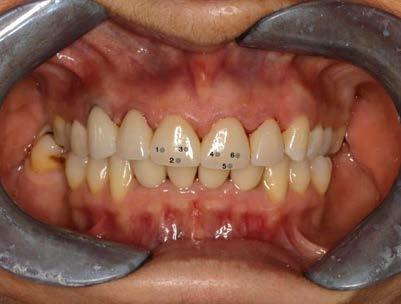

Se realizó un segundo análisis con las coronas ya cementadas en boca, únicamente de los incisivos centrales superiores, ya que uno fue confeccionado con disilicato de litio y el otro con zirconio. En este caso obtuvimos como resultado en la corona de disilicato de litio: del color rojo: 172, del color verde: 148 y en cuanto al color azul: 123. En la corona de zirconio obtuvimos del color rojo: 171, del color verde: 143, y del color azul: 119; en la escala de 0 a 255 que arroja la aplicación de Adobe Photoshop.

Podemos afirmar que también hubo variación y a pesar de utilizar 2 tipos de cerámicas diferentes, se logró obtener un buen mimetismo, dando como resultado un resultado satisfactorio para la paciente.

Se muestra un análisis comparativo de las coronas de los incisivos centrales, las cuales fueron confeccionadas, una con disilicato de litio, y la otra con zirconio.

Figura 3. Coronas ya cementadas.

Tabla 2. Análisis de las coronas ya cementadas. Se muestra un análisis comparativo de las coronas de los incisivos centrales, las cuales fueron confeccionadas, una con disilicato de litio y con zirconio.